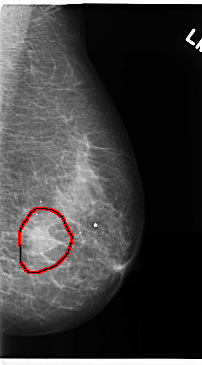

C_0216_1.LEFT_MLO

LEFT_MLO LINES 4744 PIXELS_PER_LINE 2624 BITS_PER_PIXEL 12 RESOLUTION 50 OVERLAY

FILE: C_0216_1.LEFT_CC.OVERLAY

TOTAL_ABNORMALITIES 1

ABNORMALITY 1

LESION_TYPE MASS SHAPE IRREGULAR MARGINS ILL_DEFINED

ASSESSMENT 5

SUBTLETY 5

PATHOLOGY MALIGNANT

TOTAL_OUTLINES 1

BOUNDARY